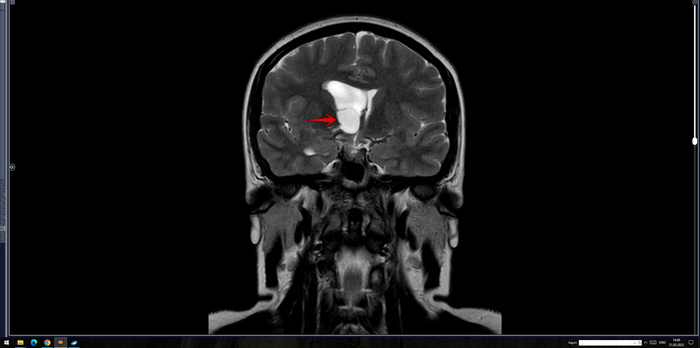

В расширенном турецком седле определяется солидное объемное образование неоднородно повышенного МР-сигнала на Т2 ВИ, размерами до 30 х 25 х 19 мм, неоднородно копит контраст. Образование распространяется в область кавернозных синусов по ходу С5 С6 сегментов внутренних сонных артерий, муфтообразно охватывая их до 70% окружности справа и до 50% окружности слева. Внутренние сонные артерии на уровне образования не сужены. Образование интимно прилежит к задним базальным отделам прямых извилин и зрительному перекресту, больше справа, без его оттеснения. Воронка гипофиза утолщена, отклонена вправо.На этом фоне нормальная структура гипофиза четко не определяется, вероятно, оттеснена вправо и кзади.

Заключение: МР- картина образования гипофиза, соответствует макроаденоме средних размеров с супра- и латероселлярным характером роста. Рек-но: конс. нейрохирурга.